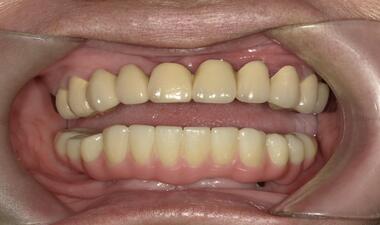

Full Arch術前術後 / 案例一

術後

裝戴固定下顎Full Arch假牙